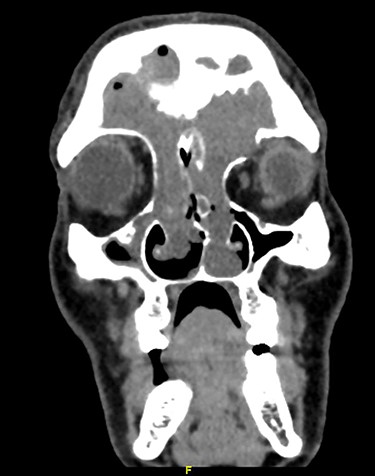

Neck computed tomography (CT) scan performed first and showed expansile soft tissue lesion involving frontal and ethmoid sinuses extending to nasal cavity. There was associated left FS bony erosion and left orbital extension. Mild mucosal thickening of maxillary sinus is also noticed (Fig. 1).